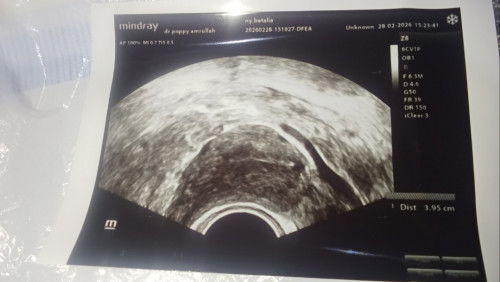

Hai bunda bunda hebat apakah ada yang sama Bun masih menanti sebuah keajaiban dari Allah, saya kuret bulan Maret kemarin usia 5w dan Agustus kemarin promil tapi belum berhasil 🥺 di cek ke obgyn katanya Alhamdulillah rahim sehat dan insyaallah siap untuk kehamilan berikutnya. Tapi insyaallah saya percaya semua akan indah pada waktunya dan saya sedang menunggu kunfayakun nya Allah, apakah ada yang sama Bun setelah kuret lama belum dikasih kepercayaan, dibawah itu foto USG pas keguguran kemarin ya. #mohonbantujawabbunda #Sharingdong_Bund